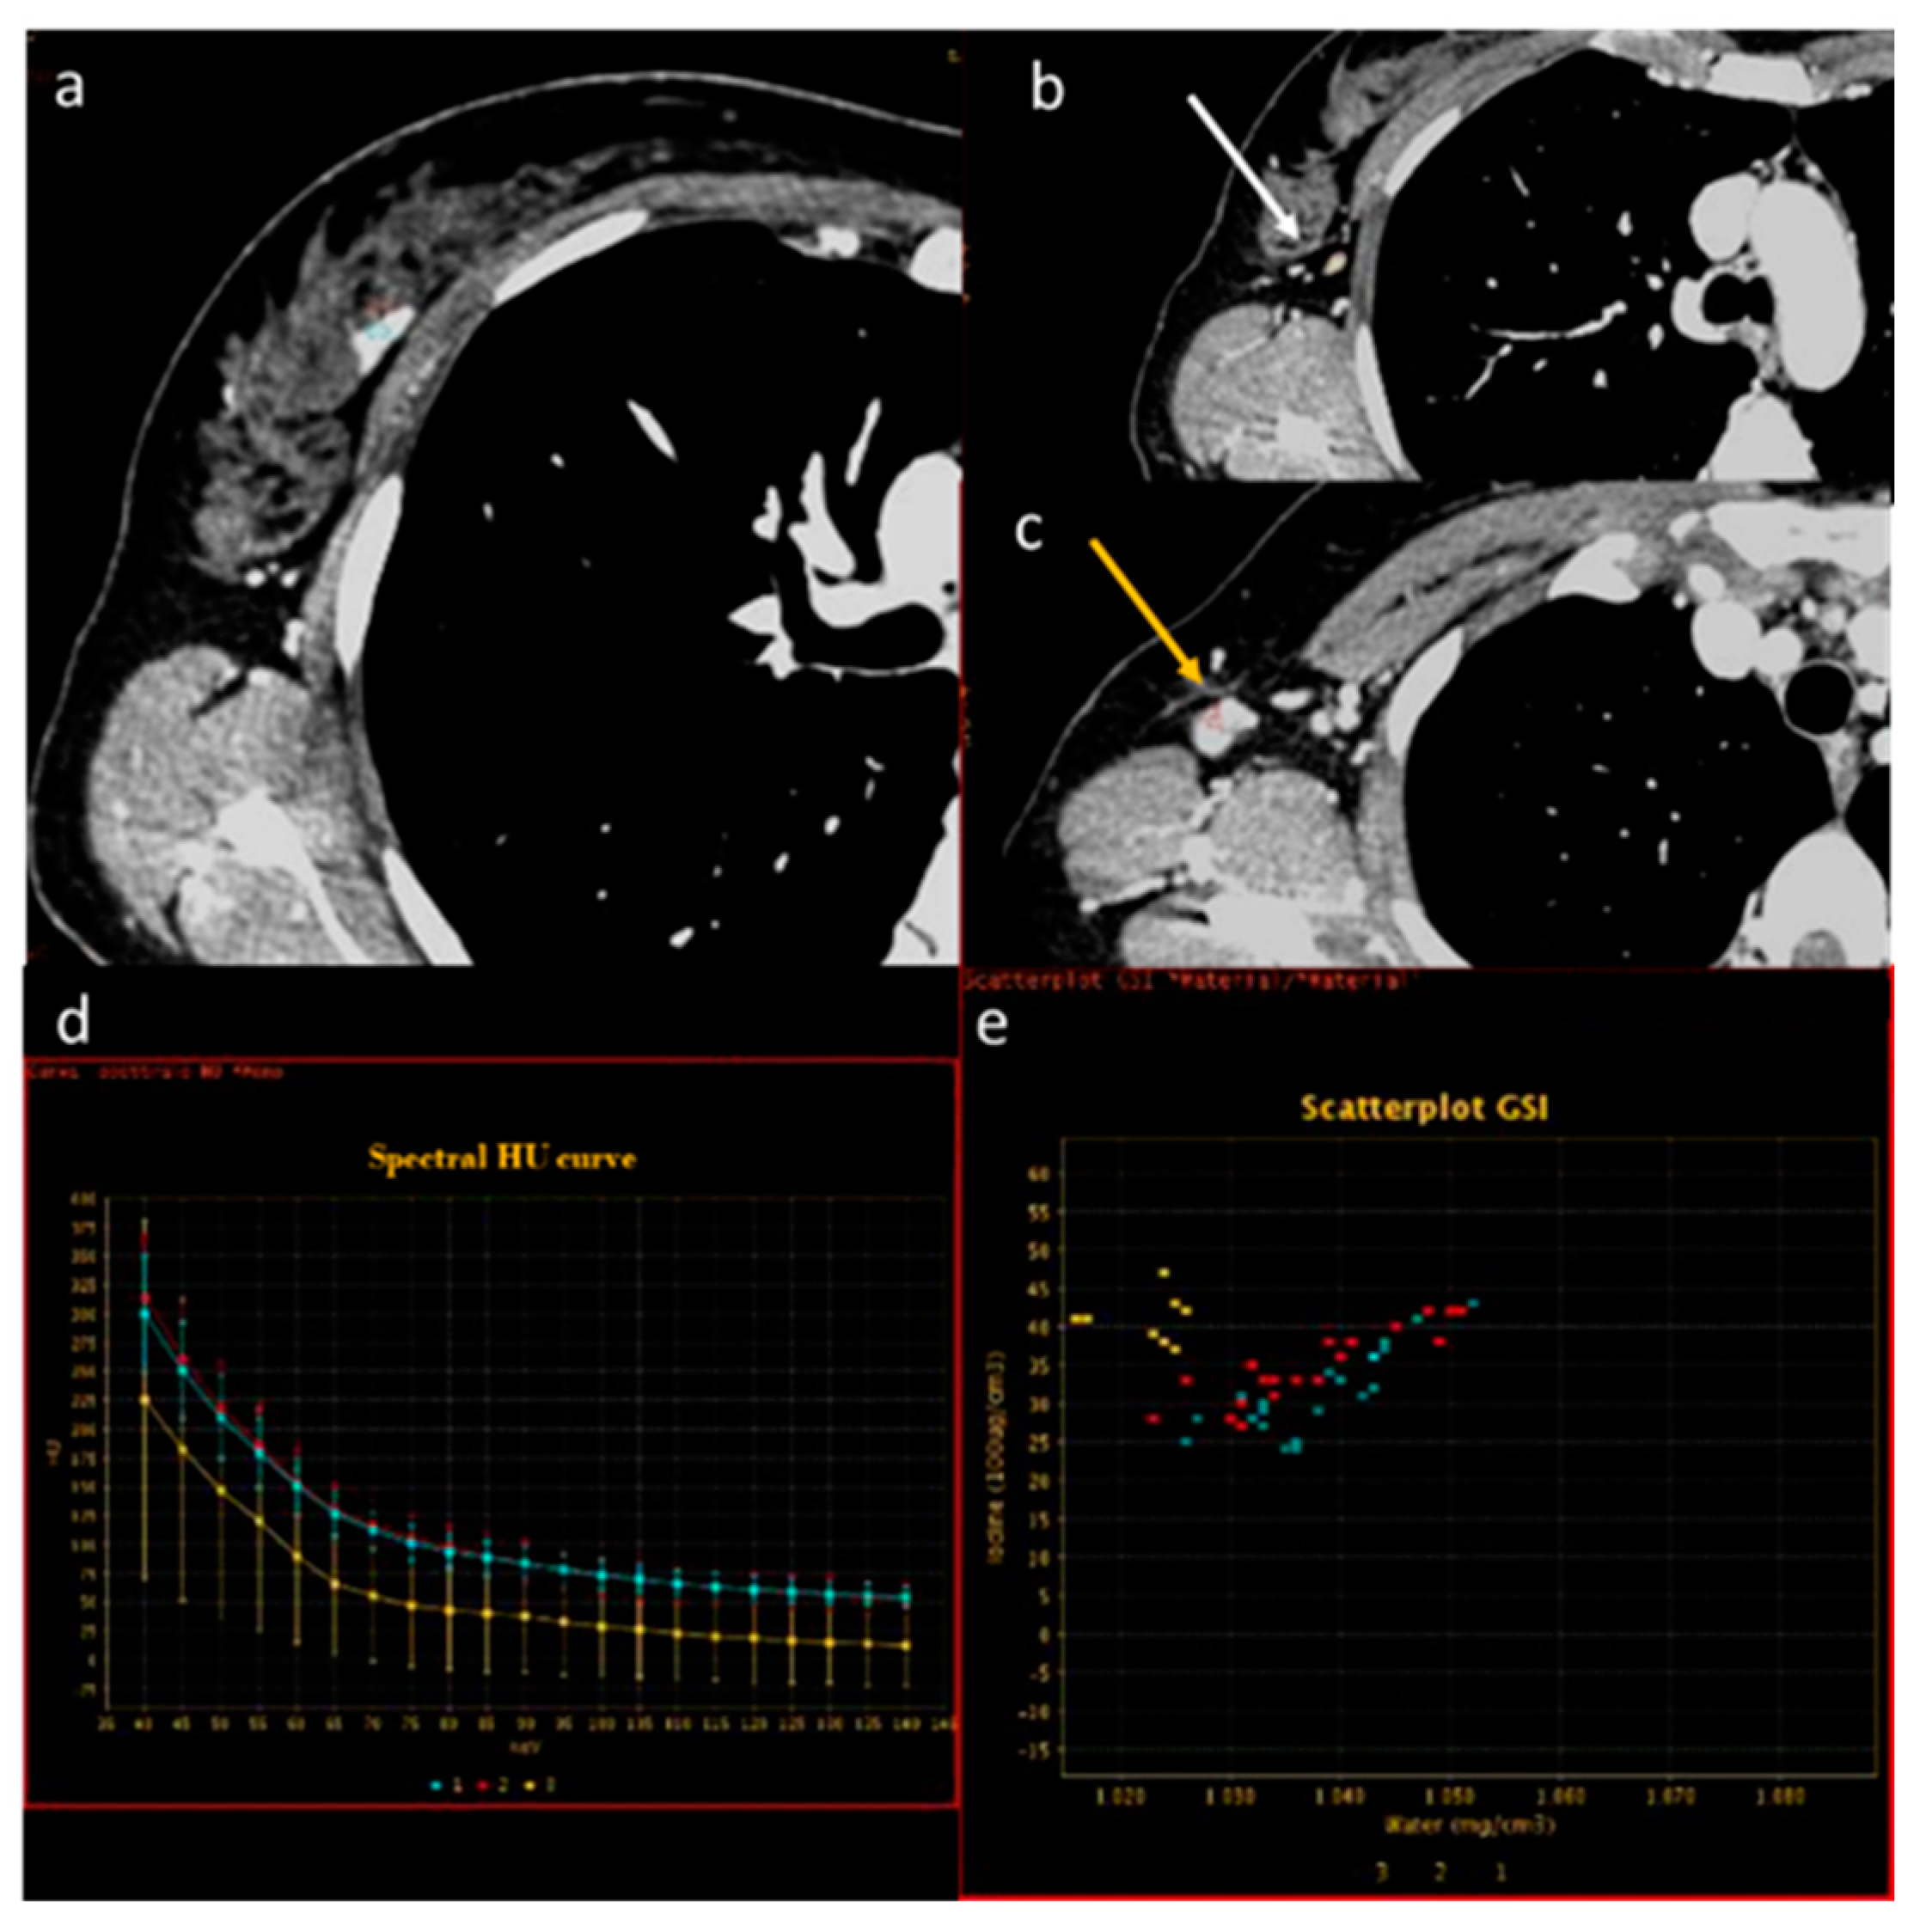

- Li, W.; Liu, M.; Yu, F.; Zhu, W.; Yu, X.; Guo, X.; Yang, Q. Detection of left atrial appendage thrombus by dual-energy computed tomography-derived imaging biomarkers in patients with atrial fibrillation. Front. Cardiovasc. Med. 2022, 9, 809688. [Google Scholar] [CrossRef] [PubMed]